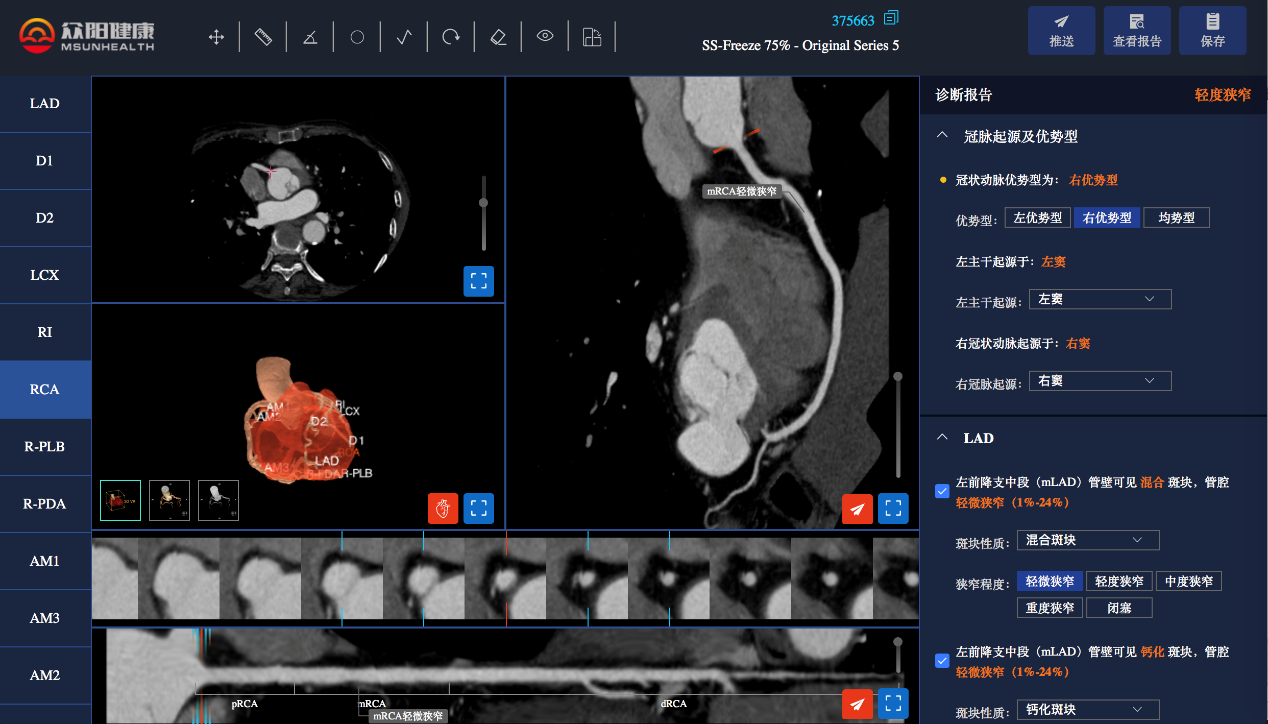

应用案例